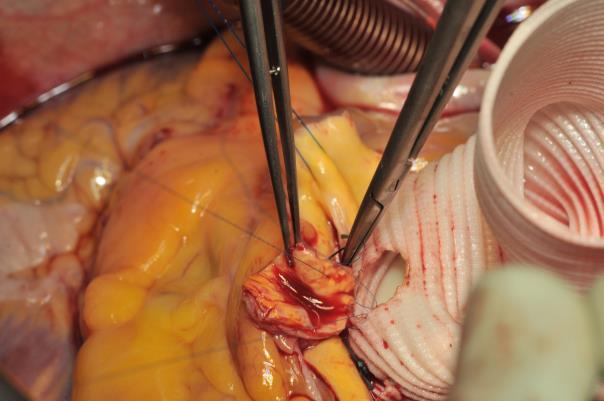

The procedure starts with the proximal suture of the composite graft prosthesis to the aortic annulus using separated mattress suture of 2.0 Ethibond backed with small Teflon pledgets. The first suture is placed at the level of the commissure between the left and right coronary sinuses and the following are stitched in a clockwise fashion (Image 1). The sutures are placed through the annulus with the pledgets left either on the aortic side thus everting the annulus, but in small annular diameters. The author prefers to stich these sutures from the ventricular side to the aorta, therefore the pledgets lie under the aortic annulus. Then the sutures are placed through the sewing ring of the composite graft prosthesis (Image 2) which is later on parachuted down to the aortic annulus (Image 3). The sutures are then tightened and the valve is placed into the outflow tract of the left ventricle (this provides excellent hemostasis).

Image 2: The sutures are passed through the sewing cuff of the valve. In this case, the Teflon pledgets were placed below the aortic annulus. Alternatively, the stitches can be performed from the aortic side (outside-in) leaving the Teflon pledgets outside of the blood flow. This is especially favorable in case when the size of the aortic annulus has to be reduced.